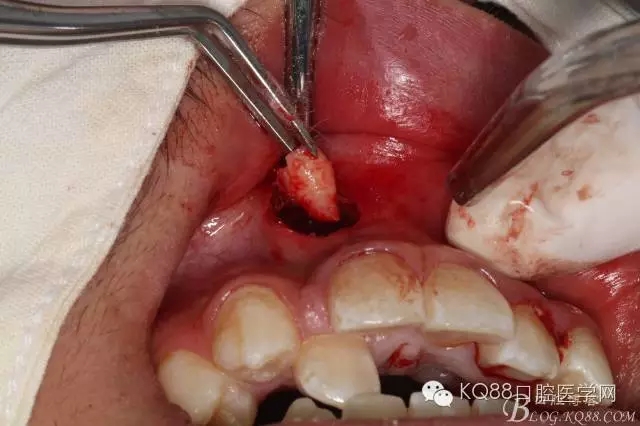

圖5.經(jīng)過(guò)仔細(xì)認(rèn)真的術(shù)前CBCT影像檢查分析,考慮手術(shù)進(jìn)路及操作性,局部浸潤(rùn)麻醉下,遂從唇側(cè)前庭溝處做弧形小切口、翻瓣。渦輪鉆去骨后的臨床情形:完美的弧形切口。去除唇側(cè)的骨板、顯露出部分多生牙的牙根和少量牙冠,位置之高,令人吃驚、一定要注意11的牙根,防止損傷11根尖。